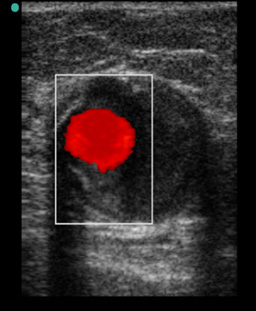

Peripheral IV (PIV) Thrombus Transverse with Color Image